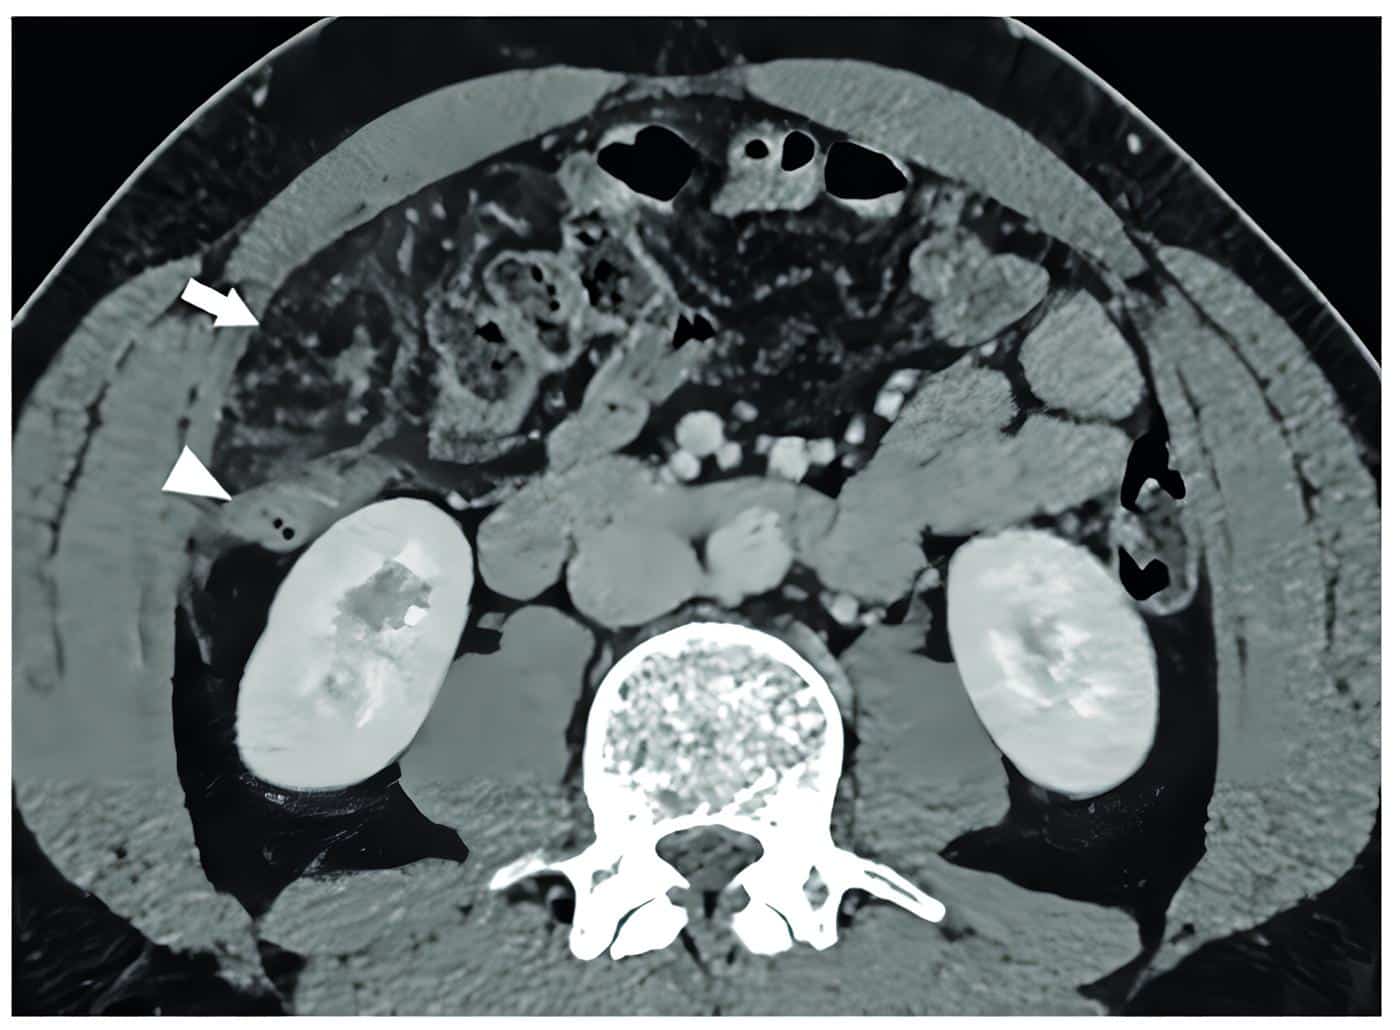

Ante la persistencia del dolor se decidió complementar los estudios con tomografía computarizada de abdomen con y sin contraste intravenoso (figuras 1 y 2) donde se aprecia infarto del omento, para lo que se inicia tratamiento médico conservador.

Figura 1. Tomografía de abdomen con contraste en fase venosa, corte axial, donde se observa a nivel de flanco derecho una alteración en la densidad del epiplón mayor, bien delimitada por un halo hiperdenso (flecha). Contacta hacia atrás con el colon ascendente, el cual presenta paredes discretamente engrosadas, de aspecto inflamatorio, desproporcionadamente menor a la alteración del epiplón (punta de flecha). Fuente: fotografías tomadas por los autores.